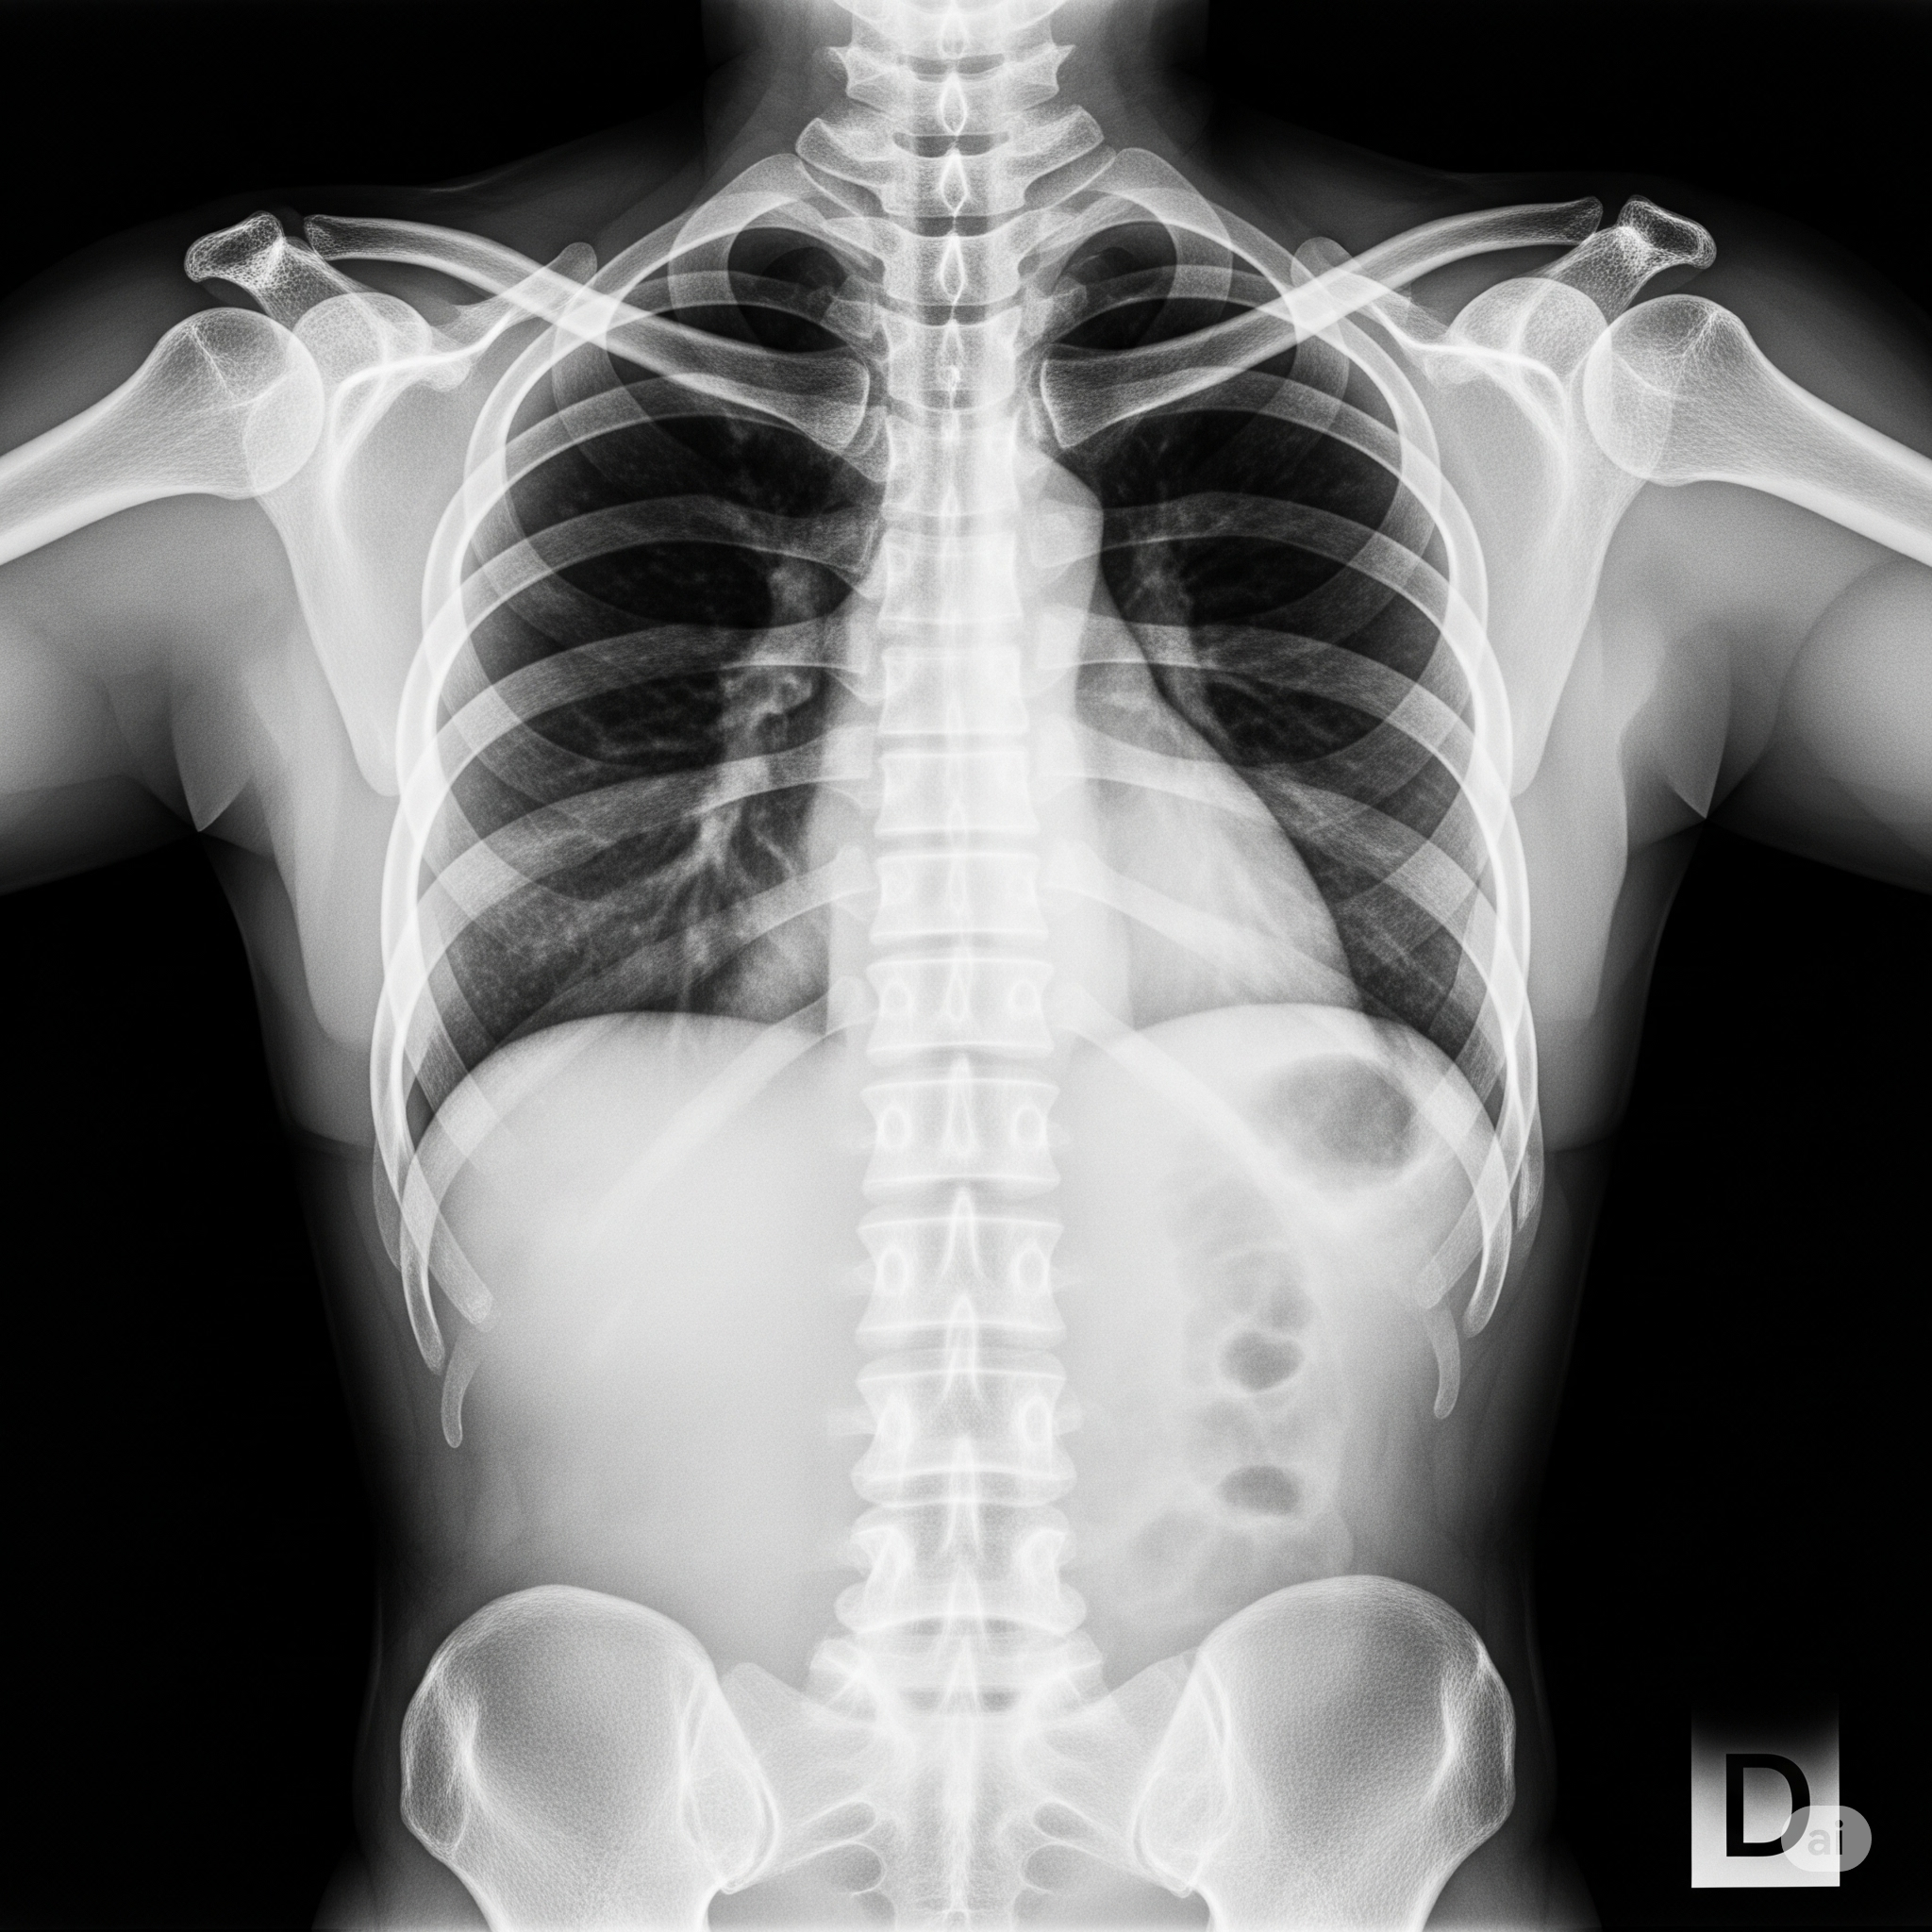

| 흉부 방사선 (X-ray) | 폐렴 여부 확인 가능 |